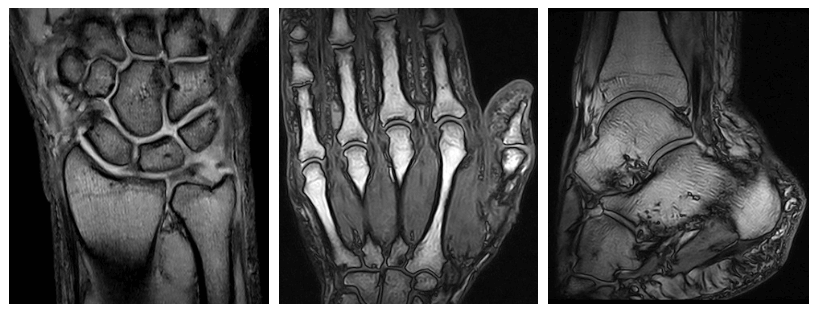

Risonanza Magnetica Aperta

Il Poliambulatorio San Camillo di Bologna è dotato di una Risonanza Magnetica Osteo-articolare Aperta.